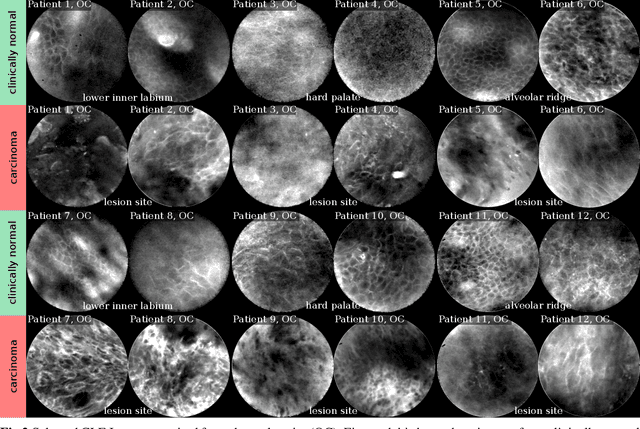

Abstract:Oral Squamous Cell Carcinoma (OSCC) is a common type of cancer of the oral epithelium. Despite their high impact on mortality, sufficient screening methods for early diagnosis of OSCC often lack accuracy and thus OSCCs are mostly diagnosed at a late stage. Early detection and accurate outline estimation of OSCCs would lead to a better curative outcome and an reduction in recurrence rates after surgical treatment. Confocal Laser Endomicroscopy (CLE) records sub-surface micro-anatomical images for in vivo cell structure analysis. Recent CLE studies showed great prospects for a reliable, real-time ultrastructural imaging of OSCC in situ. We present and evaluate a novel automatic approach for a highly accurate OSCC diagnosis using deep learning technologies on CLE images. The method is compared against textural feature-based machine learning approaches that represent the current state of the art. For this work, CLE image sequences (7894 images) from patients diagnosed with OSCC were obtained from 4 specific locations in the oral cavity, including the OSCC lesion. The present approach is found to outperform the state of the art in CLE image recognition with an area under the curve (AUC) of 0.96 and a mean accuracy of 88.3% (sensitivity 86.6%, specificity 90%).